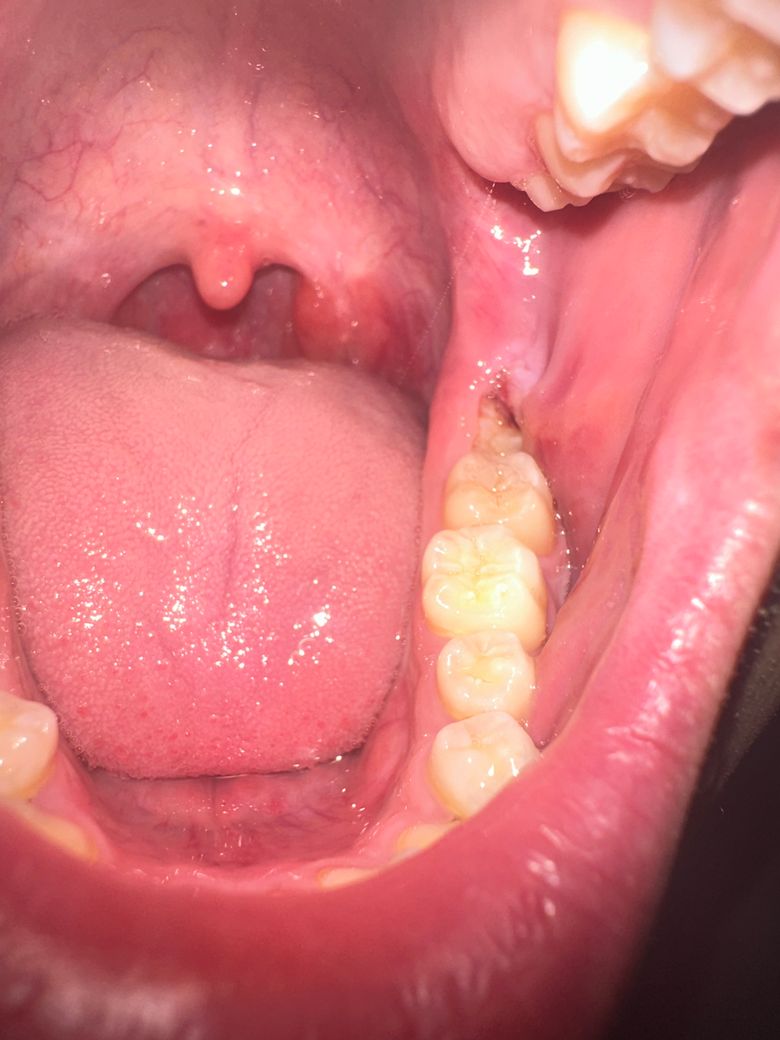

잇몸부음 진짜 너무 아파서 그런데 답변부탁드립니다

제가 너무 아파서 치과를 다녀왔는데 사랑니 뽑아야된다고 하더군요 근데 이게 혹시 사랑니 말고 다른원인이 있는건가요 제 잇몸이 부은게 한 4-5일째 게속 더 부풀어오르고 오늘 먹은 항생제와 진통제는 약이 듣질않네요 아파 죽겠어요

부분매복 사랑니로 인한 치관주위염이 의심되나 일반적인 치관주위염은 항생제로 잇몸 부종, 통증은 개선됩니다. 현 상태로는 발치를 진행해도 마취가 잘안되어 고생할 수 있으니 더 강한 항생제 처치를 요합니다.